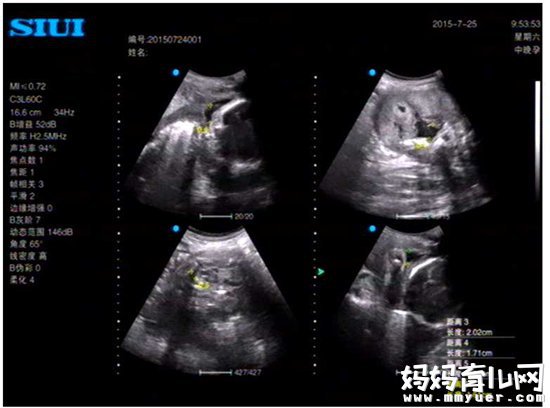

1、B超检查。

B超检查是诊断羊水过少的主要方法,包括定性诊断和半定量诊断。B超下发现羊水量明显减少、羊水和胎儿界面不清、胎儿肢体明显聚集重叠即可以做出羊水过少的定性诊断。

定性诊断后通过进一步测量羊水池的深度对羊水过少做出半定量诊断。妊娠28~40周期间,B型超声测定最大羊水池径线稳定在5.1cm±2.0cm范围,若最大羊水池垂直深度(AFV)≤2cm为羊水过少,≤1cm为严重羊水过少。